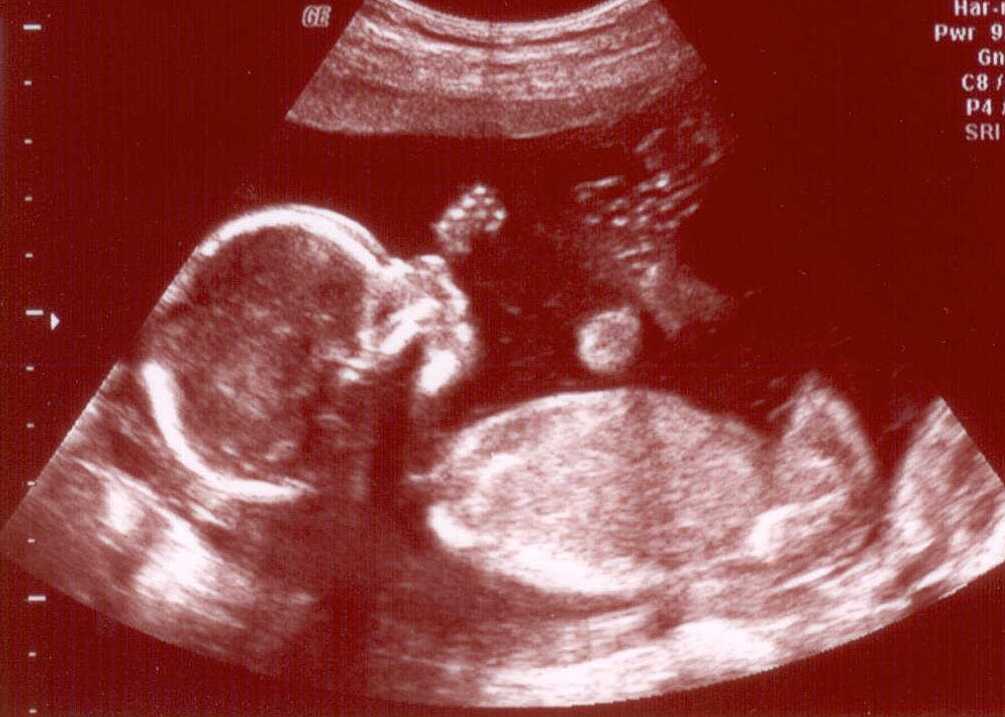

Ketchupeffekten i full effekt. Vi tänkte att det vore roligt för Charlie att ha ett syskon som inte är så mycket yngre. Slutet av januari är det sagt, men de har ju svårt att hålla tiden de där rackarna. Jag tror det var våran ultraljudstant som sa att det bara är 5% som kommer i tid…

Så, betting på kön och tid för nedkomst kan börja